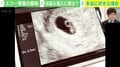

「すんげぇの売られてた」 女性が妊娠時に撮影する胎児のエコー写真がフリマサイトに出品 一体、誰がなんのために使うのか?ABEMAヒルズ| -